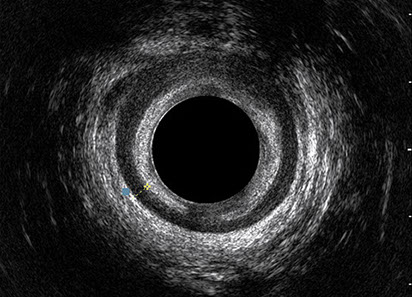

L’ecografia transanale è un esame diagnostico per immagini che consiste nell’introduzione di un trasduttore ad ultrasuoni. Le immagini qualitativamente migliori del canale anale sono ottenute usando un trasduttore rotante, montato in un manipolo rigido, che fornisce un’immagine a 360°. Con le apparecchiature più moderne è anche possibile ottenere immagini tridimensionali.

L’ecografia transanale permette di distinguere la sottomucosa che riveste il canale anale, lo sfintere anale interno, e lo sfintere anale esterno.

Le principali indicazioni all’esecuzione di tale esame sono lo studio dell’integrità delle strutture muscolari nei casi di incontinenza fecale, lo studio topografico dei processi settici perianali (ascessi e fistole) e lo studio dei processi proliferativi epiteliali (carcinoma anale).